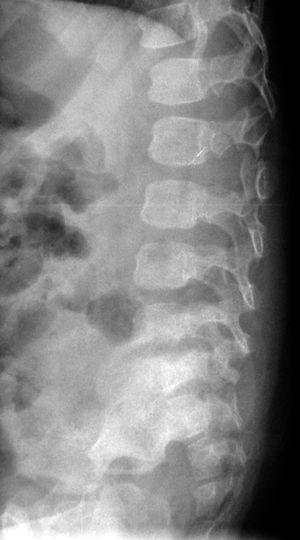

El hemograma, los tiempos de coagulación y la proteína C reactiva fueron normales. La velocidad de sedimentación globular (VSG) de 42 mm/h, indicaba un probable proceso inflamatorio. En la radiografía de columna vertebral se observó una mala definición de los platillos vertebrales inferior de L5 y superior de S1, con aparente esclerosis (fig. 1). La gammagrafía con 99mTc mostró un aumento de captación leve, de morfología lineal, en área teórica de las carillas articulares de cuerpos vertebrales L5-S1 (fig. 2).

Figura 1. Radiografía de columna vertebral, se observa esclerosis de platillos vertebrales inferior L5 y superior S1 y disminución del espacio discal.